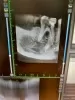

Врач зачистил каналы зуба, сделал рентген и отправил домой. В этот день у меня начался отпуск, и мы улетели в другой город. Там я по острой боли пришла в местную поликлинику. Там после рентгена сделали надрез десны и поставили дренаж на 2 дня. Через два дня состояние стабилизировалось и ушли боли. На следующем приёме почистили каналы, поставили лекарство и временную пломбу. Спустя 3 дня лекарство сменили и сказали, что пломбу нужно менять через месяц. Сделали рентген и сказали, всё хорошо.

Спустя неделю, уже в другом городе, обнаружила шишку на десне соседнего зуба. Шишка увеличилась, но не беспокоила болями. Я снова пришла уже в очередную клинику. Там сделали снимки. Сказали, нужно делать резекцию корня зуба или вообще удалять зуб. После этого начали активно продвигать рекламу своей клиники, что очень смутило.